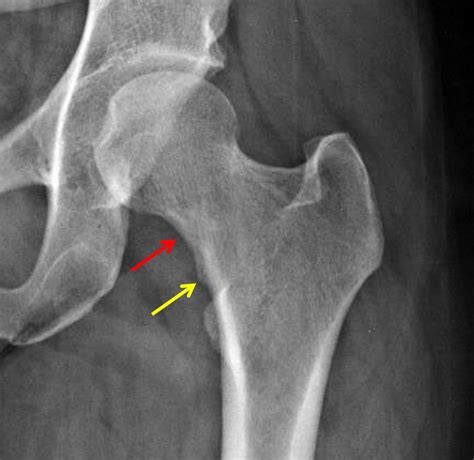

Fractures of the neck of femur are common, particularly in older adults and individuals with osteoporosis. These fractures can be classified into several types based on their location and pattern:

• Subcapital Fractures: Occur just below the femoral head.

• Transcervical Fractures: Occur in the middle of the femoral neck.

• Basicervical Fractures: Occur at the base of the femoral neck, near the junction with the femoral shaft.

Fractures of the neck of femur often result from falls or high-impact trauma. They can be particularly challenging to treat due to the limited blood supply to the femoral head, which can lead to complications such as avascular necrosis.

• X-rays: To visualize the bone structure and identify fractures or degenerative changes.